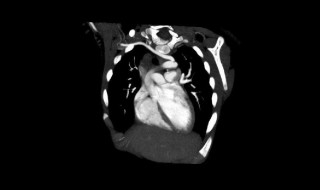

1、右迷走锁骨下动脉病症是主动脉弓部的一种先天性血管畸形,一般在颈椎和胸椎之间发病较多,大多数胎儿出生后如果没有特殊症状,对身体健康是没有严重影响的,不需要采用特殊治疗。

2、如果出现吞咽或呼吸困难、上肢麻木疼痛冰冷等临床症状,可能是压迫了食管、气管或其他局部神经,建议先到医院拍片确诊病因,必要时可做微创手术治疗。